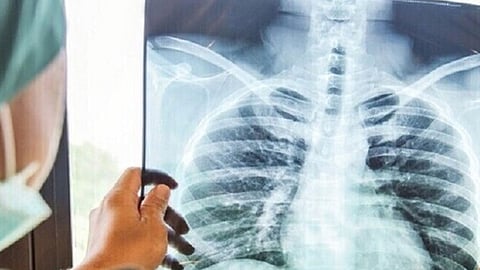

صورة بالأشعة السينية

كشفت صور صادمة بالأشعة السينية الأضرار المدمرة التي تخلفها الإصابة بفيروس «كورونا» المستجد على رئة الأشخاص غير المحصنين.

ومن خلال المقارنة بين صور للأشعة لرئة مصاب محصن باللقاحات المضادة للفيروس وآخر غير محصن، قال الدكتور عمر أوان، نائب رئيس التعليم المساعد في قسم التشخيص والأشعة في كلية الطب بجامعة ماريلاند، إن هناك فرقًا كبيرًا في صور الأشعة السينية للصدر التي نراها في المرضى الذين تم تطعيمهم بالكامل، والذين ثبتت إصابتهم ولم يتم تطعيمهم، حسب «روسيا اليوم».

وأوضح: «يمكن أن نرى في الشخص الذي حصل على اللقاح، أن الكثير من الرئة سوداء، وهذا شيء جيد لأن الأسود يدل على الهواء، إن عبء المرض أو عبء العدوى يكون أكثر وضوحًا في الفرد غير المحصّن مقابل الشخص الملقح».

وتحدث أوان عن خطورة الأعراض التي تظهر عند الإصابة، لدى المحصنين وغير المحصنين، وقال: «في كثير من الأحيان، يعاني من لم يقع تلقيحهم من ضيق شديد في التنفس. وقد يحتاجون إلى علاج بالأكسجين. وهناك اتجاه أكبر لديهم لدخول وحدة العناية المركزة».